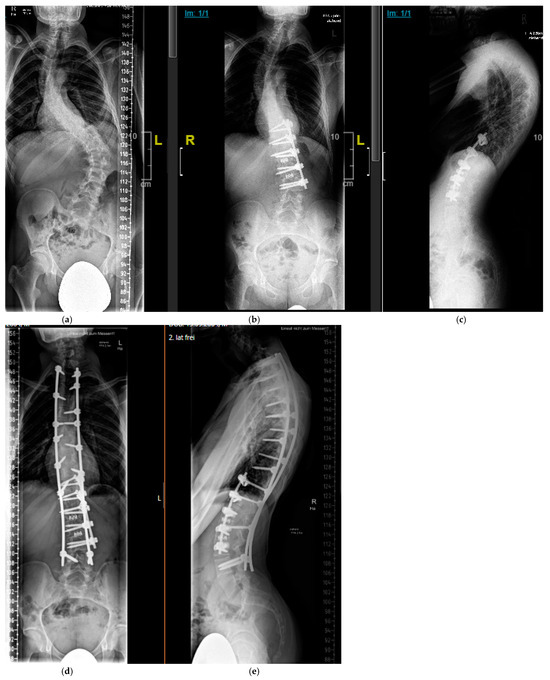

4.2.1. “Early Onset Spinal Deformity”

5.2.1. Growth-Preserving Techniques